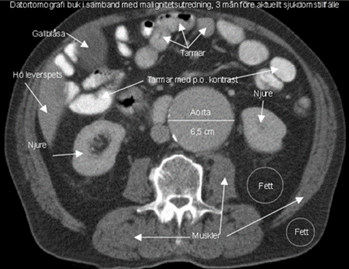

Hjärtat är allmänförstorat. Lungkärlen är vida och det finns ökad mängd pleuravätska bilateralt. Det finns spridda interstitiella och basalt på höger sida även alveolära infiltrat.

• Hjärtinkompensation.

Lungödem och normal lunga